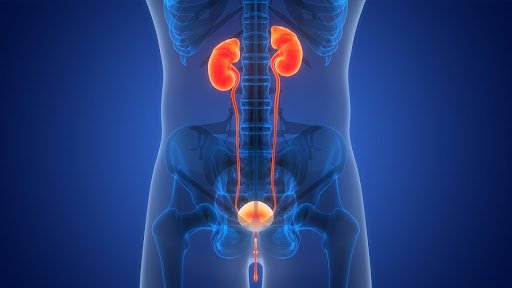

Urologist and nephrologist in Nagpur

Urologist and nephrologist

Our Urology Services

We specialize in treating a range of urological conditions, including:

Our Nephrology Services

Our nephrologists provide expert care for complex kidney-related conditions, such as: